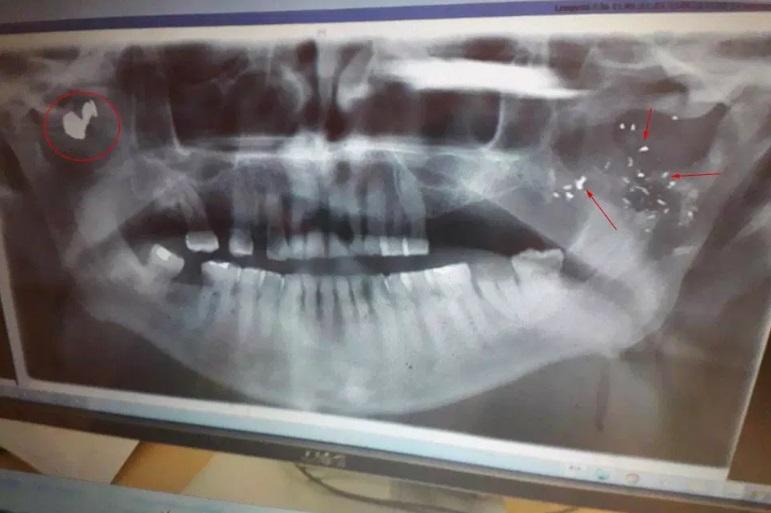

Bărbatul, Ray Weatherall, în vârstă de 53 de ani, nu avea idee că soția lui, Hayley, în vârstă de 32 de ani, și cel mai bun prieten al lui, Glenn Pollard, în vârstă de 49 de ani, aveau o aventură și plănuiau să îl ucidă. Ray Weatherall a supraviețuit în mod miraculous după ce a fost împușcat în orașul Sandwich din comitatul Kent. Glonțul l-a rănit doar la față.